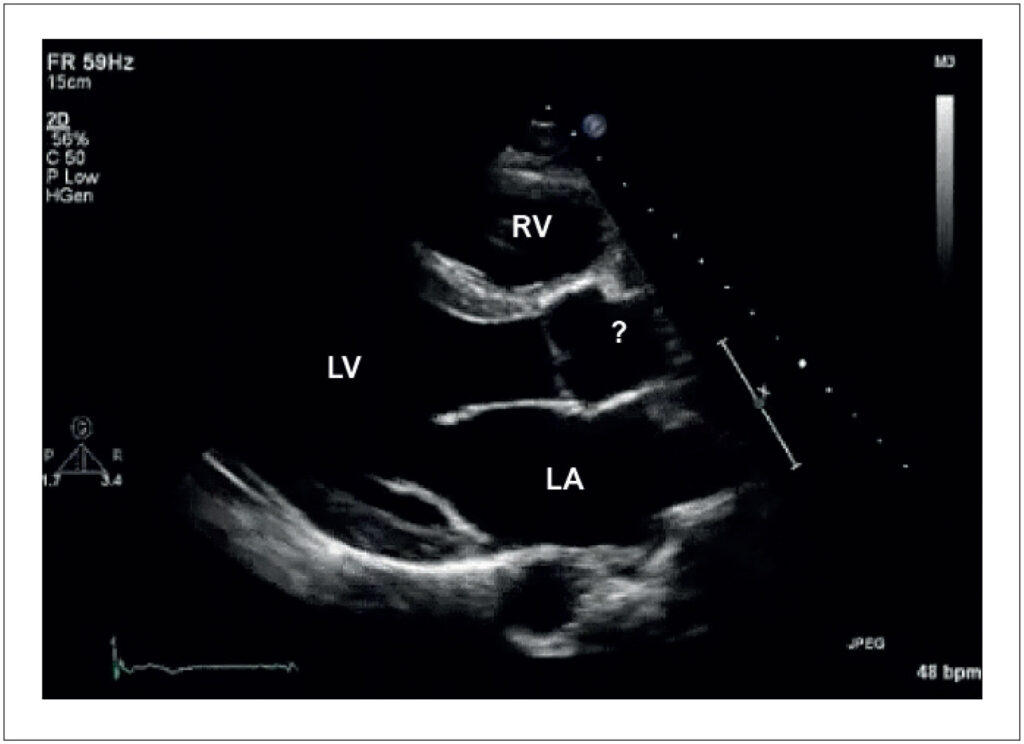

Exercise-induced adaptation may occur in amateur and professional athletes. This condition is commonly named “athlete’s heart”. The alterations observed include dilation of the heart chambers, increased myocardial thickness, improved ventricular filling, increased left ventricular trabeculation, dilation of the inferior vena cava, among others. These changes can also be observed in some heart diseases, such as dilated, hypertrophic and other cardiomyopathies (CMP). Thus, cardiac imaging tests are fundamental in identifying these alterations and in differentiating between “athlete’s heart” and possible heart disease.